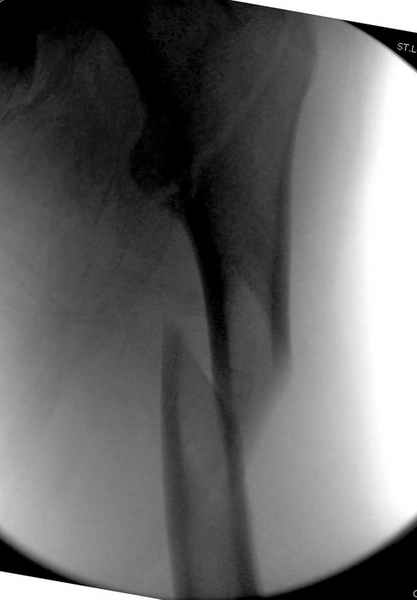

Как раз недавно у меня был примерный случай: больному 36 лет, поступил ночью, травма в результате мотоциклетной аварии, кроме чрезвертельного и спирального перелома левого бедра имеется переломы костей предплечья с этой же стороны. Скелетное вытяжение, а на следующий день больной про оперирован на ортопедическом столе с дистракцией. Чтобы не расколоть чрезвертельный перелом провели временную спицу ближе к переднему кортексу, из малого разреза костодержатель для репозиции, а фиксацию провели антиградным штифтом. Этапы операции на снимках.

Джолдас Кульджанов

DK> фиксацию провели антеградным штифтом.

Да, сейчас это и у нас самый напрашивающийся выбор. Сделали гвоздем ChM, картинки в приложении.